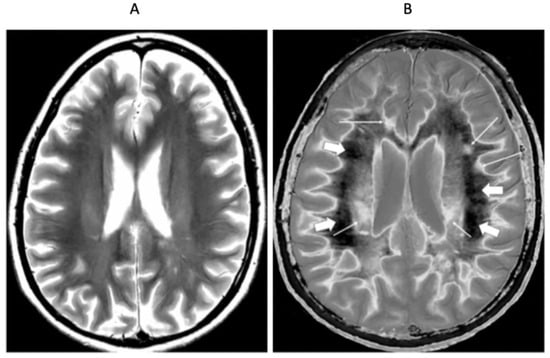

Figure 8 shows positionally matched supraventricular T2-FLAIR (Figure 8A) and narrow mD dSIR (Figure 8B) images in a patient with MS during a relapse. A single lesion is seen on the T2-FLAIR image, and this is also seen on the dSIR image (long white arrows). An additional six lesions are only seen on the dSIR image (short white arrows). Many of the lesions on the dSIR image have high signal boundaries (rims). In addition, there are bilateral symmetrical widespread relatively uniform increases in signal in white matter, with some sparing of more peripheral white matter. These are features of a high grade (4–5) (maximum grade 5) whiteout sign [6]. This differs from the normal dark appearance of white matter seen on the narrow mD dSIR image in Figure 6B. No evidence of a whiteout sign is seen on the T2-FLAIR image.

Figure 8.

Thirty-two-year-old female patient with MS undergoing a relapse. T2-FLAIR (A) and synthetic narrow mD dSIR (B) images. On the T2-FLAIR image, one lesion is seen (long arrow). The surrounding white matter appears normal. On the dSIR image (B), the lesion shown on the T2-FLAIR image is seen (long arrow) as well as six other lesions (short arrows). Most of the white matter in (B) is high signal corresponding to a high grade 5 (out of 5) whiteout sign [7]. This is in contradistinction to the appearance of the peripheral white matter in the patient with MS in remission shown in Figure 6B. where the peripheral white matter is low signal.